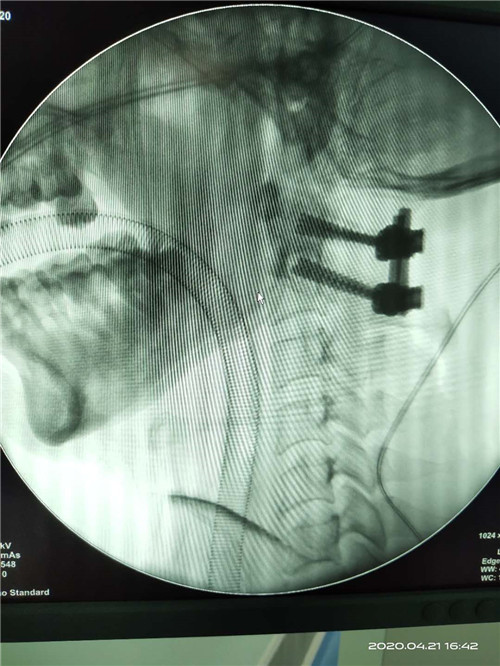

术中图片如下

微信图片_20200507143102

微信图片_20200507143107

术后透视

微信图片_20200507143111